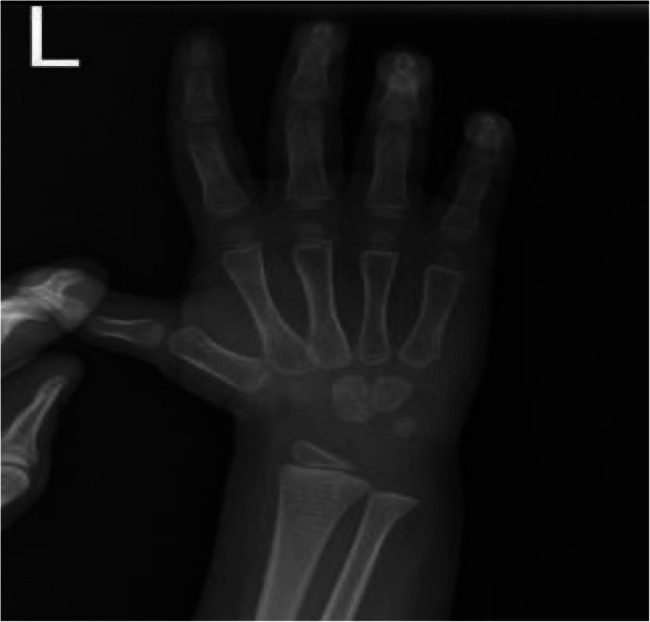

先天性甲状腺功能减退症(CH)是一种常见的疾病,如果不及时诊断和治疗,可导致婴儿显著的神经发育问题。Van Wyk和Grumbach综合征(VWGS)以甲状腺功能减退、性早熟和卵巢肿块为特征,由于诊断资源有限,在中低收入国家(LMICs)经常被误诊。这个病例强调了系统性的挑战,包括延迟诊断和不必要的手术转诊。我们报告一个8岁的女孩被诊断为Van Wyk-Grumbach综合征,其特征是严重的甲状腺功能减退,同性性早熟和卵巢过度刺激。她的症状包括阴道出血、腹胀和明显的肥胖并发育不良。检查显示严重甲状腺功能减退(TSH: 96 mU/L)和双侧卵巢囊肿增大。在开始左旋甲状腺素治疗后,患者表现出显著的临床改善,包括腹部肿胀减轻和甲状腺功能正常化。本病例强调了在儿童卵巢肿块鉴别诊断中考虑甲状腺功能减退的重要性,特别是在缺乏新生儿筛查方案的地区,以防止不必要的手术干预并确保对病情的适当管理。

Congenital hypothyroidism (CH) is a prevalent condition that can lead to significant neurodevelopmental issues in infants if not diagnosed and treated promptly. Van Wyk and Grumbach Syndrome (VWGS), characterized by hypothyroidism, precocious puberty, and ovarian masses, is often misdiagnosed in low- and middle-income countries (LMICs) due to limited diagnostic resources. This case highlights systemic challenges, including delayed diagnosis and unnecessary surgical referrals.We present an 8-year-old girl diagnosed with Van Wyk-Grumbach syndrome, characterized by severe hypothyroidism, isosexual precocious puberty, and ovarian hyperstimulation. She exhibited symptoms including vaginal bleeding, abdominal distention, and marked obesity with stunted growth. Investigations revealed severe hypothyroidism (TSH: 96 mU/L) and enlarged bilateral ovarian cysts. After initiating levothyroxine therapy, the patient demonstrated remarkable clinical improvement, including reduced abdominal swelling and normalizing thyroid function. This case underscores the importance of considering hypothyroidism in differential diagnoses of ovarian masses in children, especially in regions lacking newborn screening protocols, to prevent unnecessary surgical interventions and ensure appropriate management of the condition.